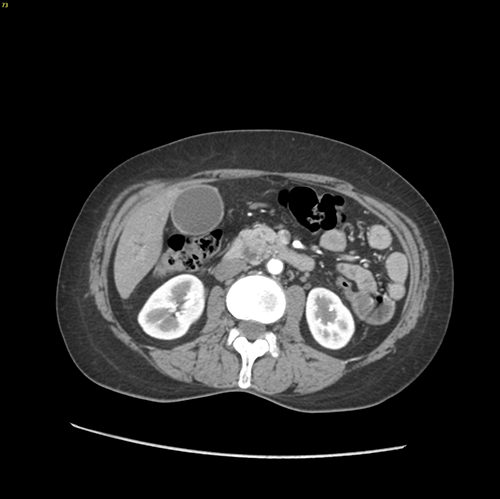

胰头癌-胰十二指肠切除